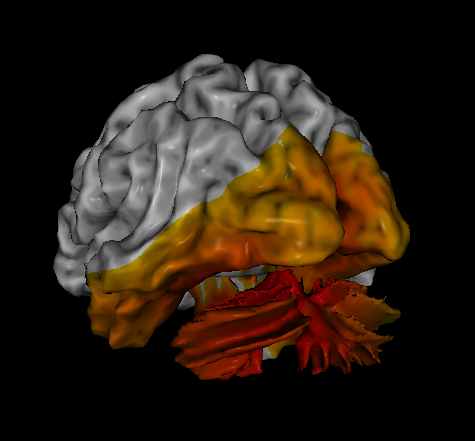

How a head injury affects functioning depends largely on the location, intensity, and frequency of the injuries. QEEGs show an increase in slower brain waves like delta and theta in damaged brain regions. These waves are reparative in nature and are at frequencies essential to cell growth. However, in the case of some injuries, these slower waves can stick around and negatively impact the overall functioning of the brain.

It is especially common to see EEG slowing in the temporal lobes after concussions, regardless of the site of the impact. This observed slowing is thought to contribute to the memory, emotional processing, and language processing problems that many individuals with brain damage experience.

swLORETA brain scan showing a concussion